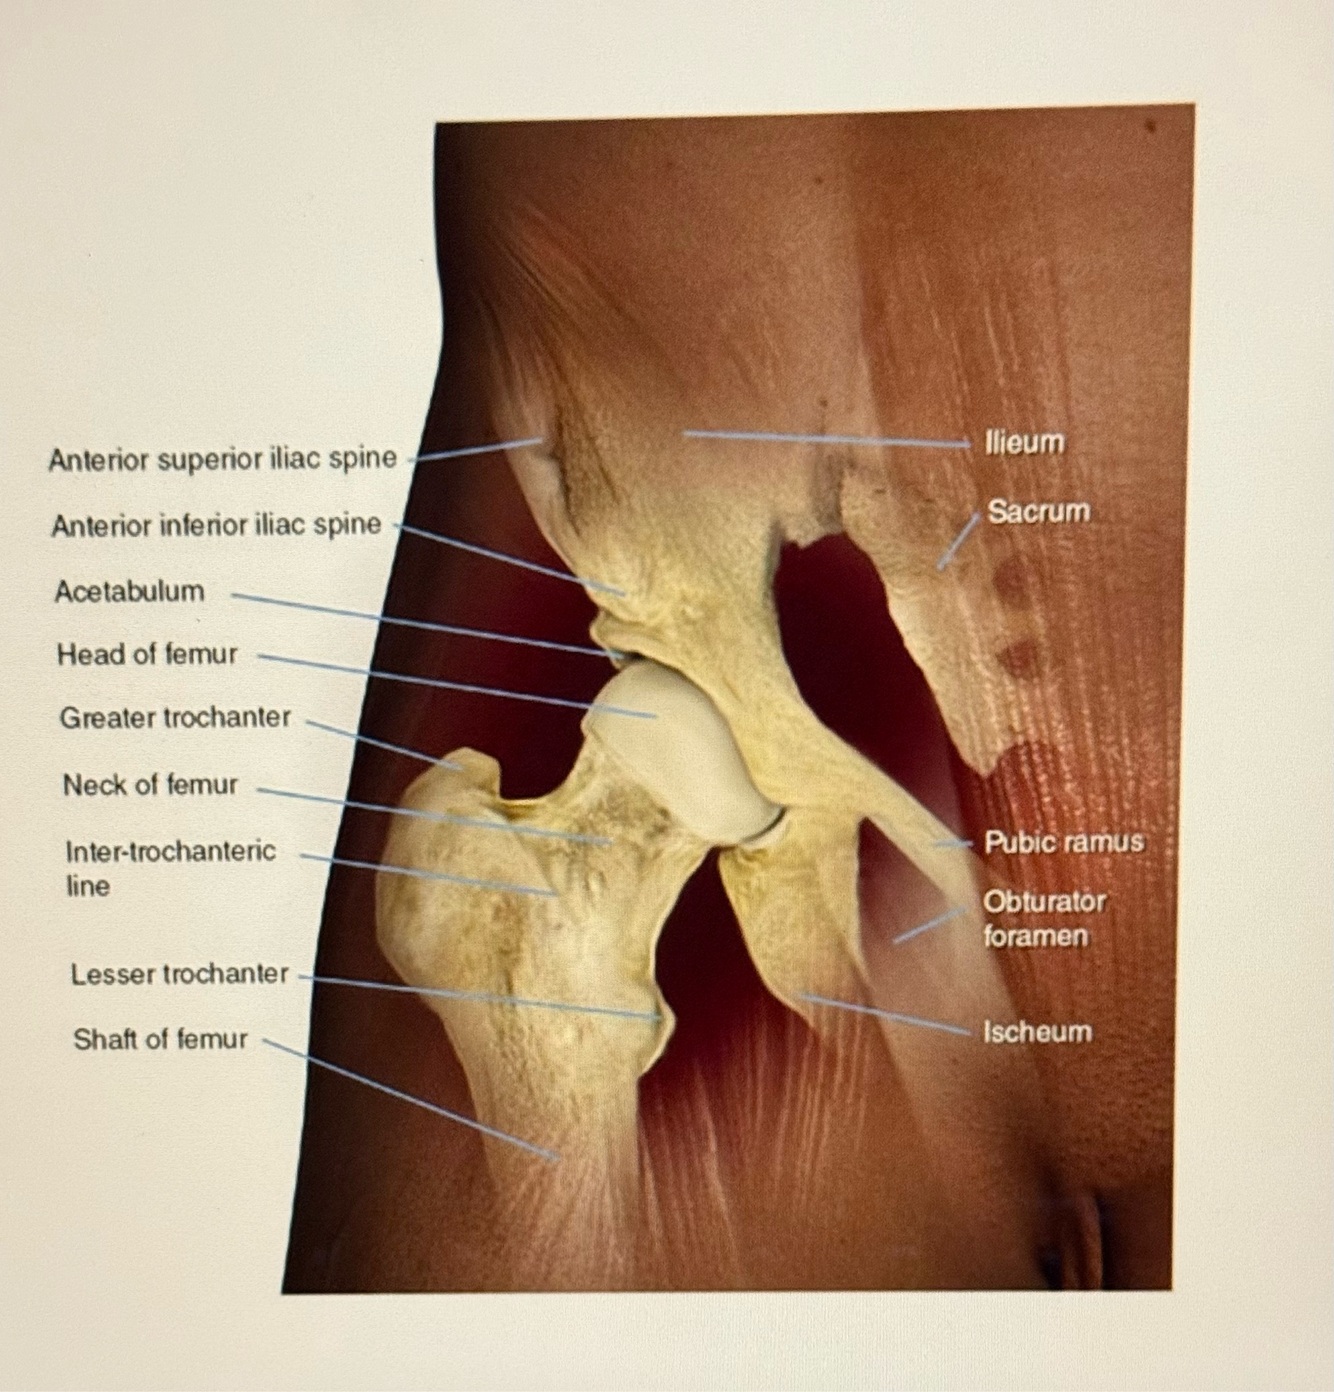

Letter D points to

A

Acetabulum

Letter E points to the

Ischium

3

Q

Letter G points to the

Superior pubic ramus